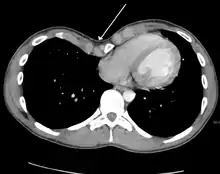

Physiologically, increased pressure in utero, rickets and increased traction on the sternum due to abnormalities of the diaphragm have been postulated as specific mechanisms.[9] Because the heart is located behind the sternum, and because individuals with pectus excavatum have been shown to have visible deformities of the heart seen both on radiological imaging and after autopsies, it has been hypothesized that there is impairment of the function of the cardiovascular system in individuals with pectus excavatum. While some studies have demonstrated decreased cardiovascular function, no consensus has been reached based on newer physiological tests such as echocardiography of the presence or degree of impairment in cardiovascular function. However, a 2016 meta-analysis found significant evidence that surgical correction of pectus excavatum improves patient cardiac performance.[14]

Many scales have been developed to determine the degree of deformity in the chest wall. Most of these are variants on the distance between the sternum and the spine. One such index is the Backer ratio which grades severity of deformity based on the ratio between the diameter of the vertebral body nearest to xiphosternal junction and the distance between the xiphosternal junction and the nearest vertebral body.[17] More recently the Haller index has been used based on CT scan measurements. An index over 3.25 is often defined as severe.[18] The Haller index is the ratio between the horizontal distance of the inside of the ribcage and the shortest distance between the vertebrae and sternum.[19]